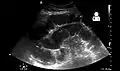

Small bowel obstruction on ultrasound.[15]

Radiological signs of bowel obstruction include bowel distension and the presence of multiple (more than six) gas-fluid levels on supine and erect abdominal radiographs. Ultrasounds may be as useful as CT scanning to make the diagnosis.[13]